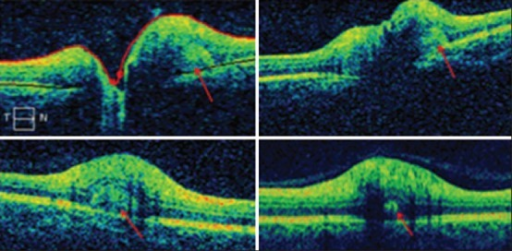

- OCT-EDI: 드루젠 직접 관찰 가능

- B-scan, OCT-EDI, FAF로 진단

- Malmqvist L, et al. OCT-EDI for optic disc drusen. Ophthalmology. 2018;125(5):723-732.